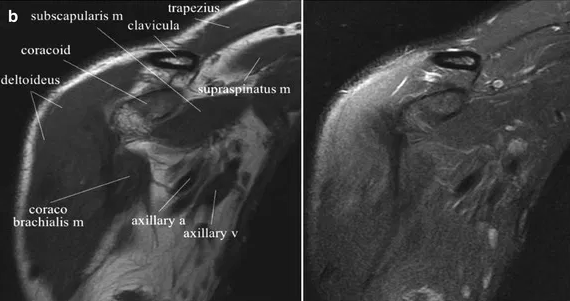

자기공명영상(MRI)은 초전도 자석, 고주파, 컴퓨터 등을 이용해 인체 조직과 혈관을 2차원 또는 3차원으로 검사하는 방법이다. 기기의 특성상 테스트 시 큰 소음이 나는 것 외에는 테스트에 따른 통증이나 부작용이 거의 없습니다. 검사가 시작되면 신체가 실린더 안으로 들어가고 신체가 느낄 수 없는 특정 무선 주파수가 검사 영역으로 전송됩니다. 수신된 정보를 컴퓨터로 처리하여 인체의 모든 부분을 단면 및 입체영상으로 재구성하여 질병의 유무를 진단하는 검사입니다. 검사를 받기 어려우신 분* 심장박동기 시술을 받으신 분* 동맥류 협착증이 있으신 분 * 신경자극기를 시술받은 분 * 인공와우 시술을 받으신 분 * 폐소공포증 환자 진찰 전 확인이 필요한 분 * 머리, 심장, 뼈에 금속 보형물을 이식한 적이 있거나 몸에 금속 파편이 있는 사람 임신 중인 경우 검사 가능성에 대해 의사와 상의하세요.* 임신 중이거나 임신 가능성이 있는 사람이 있습니다. 검사의 장점과 상대적 위험성을 고려하여 담당 의사와 상담 후 결정하시는 것이 좋습니다.* 보청기, 틀니, 머리핀, 벨트, 시계, 열쇠, 지갑, 카드, 귀금속류 등 금속류 물품을 소지한 경우 휴대폰은 검사에 방해가 될 수 있으므로 별도로 챙겨가시기 바랍니다. 안전한 곳에 보관해야 하며, 카드가 지워지거나 시계, 휴대폰 등이 파손될 수 있습니다. 단, 고정된 인공치아나 보철물은 허용됩니다.* 검사 전 금식이 필요한 성인 및 소아 복부(간, 신장, 췌장 등) (단, 산부인과 골반검사의 경우 3시간 정도 소변을 참는 것이 도움이 됩니다.) 시간.) 절차는 어떻게 진행되나요? .* 필요한 경우 진정제를 투여할 수 있으며, 검사 종류에 따라 조영제를 투여할 수 있습니다.* MRI 검사대를 기계에 삽입한 후 원통형 구조물(스캐너) 내부에서 영상화가 시작됩니다. 구조물 내부에서 이루어지기 때문에 다소 답답한 느낌이 들 수 있습니다. 테스트가 시작되면 몇 분 간격으로 소리가 들려오며, 평소처럼 차분한 마음으로 가만히 누워 있을 수 있습니다. 숨을 참고 숨을 내쉴 수 있습니다. 검사 후에는 무엇을 해야 합니까?* 검사 후에는 식사를 해도 됩니다. 드물게 조영제 사용 후 조영제에 대한 과민증이 발생할 수 있습니다. 과민반응에는 경미한 구토, 두드러기, 얼굴이 붉어지는 현상, 기침, 쉰 목소리, 콧물, 반점, 일시적인 호흡 곤란 등이 포함됩니다. 증상은 일반적으로 별다른 조치 없이 사라집니다. 출처 서울대학교병원

광주어깨. CPM재활한방병원 무릎수술 후 수정> MRI 스캔으로 이를 보완하는 것이 무엇인지 살펴보겠습니다. 광고 후 계속됩니다. 다음 주제 작성자 취소 광주허리통증 치료 좋은한의원 재생 0 좋아요 0 좋아요 공유 0:00:00 재생 음소거 00:00 00:00 실시간 설정 전체화면 해상도 currentTrack 비활성화 자막 재생 속도 NaNx 해상도 자막 설정 비활성화 옵션 텍스트 크기 배경색 재생률 0.5x 1.0x(기본값) 1.5x 2.0x 알 수 없는 오류가 발생했습니다. 도움말이 음소거되었습니다. 도움말 라이센스 이 영상은 고화질로 재생할 수 있습니다. 설정에서 해상도를 변경해보세요. 자세히 보기 0:00:00 접기/펼치기 IDD 광주감압치료병원 허리통증 치료 잘하는 광주한방병원 제2절 회사가 보상하는 항목 총액의 80%에 해당하는 금액(실제로 지급한 금액을 말한다) 본인)의 ‘항목별 공제금액’에서 규정한 의료급여의